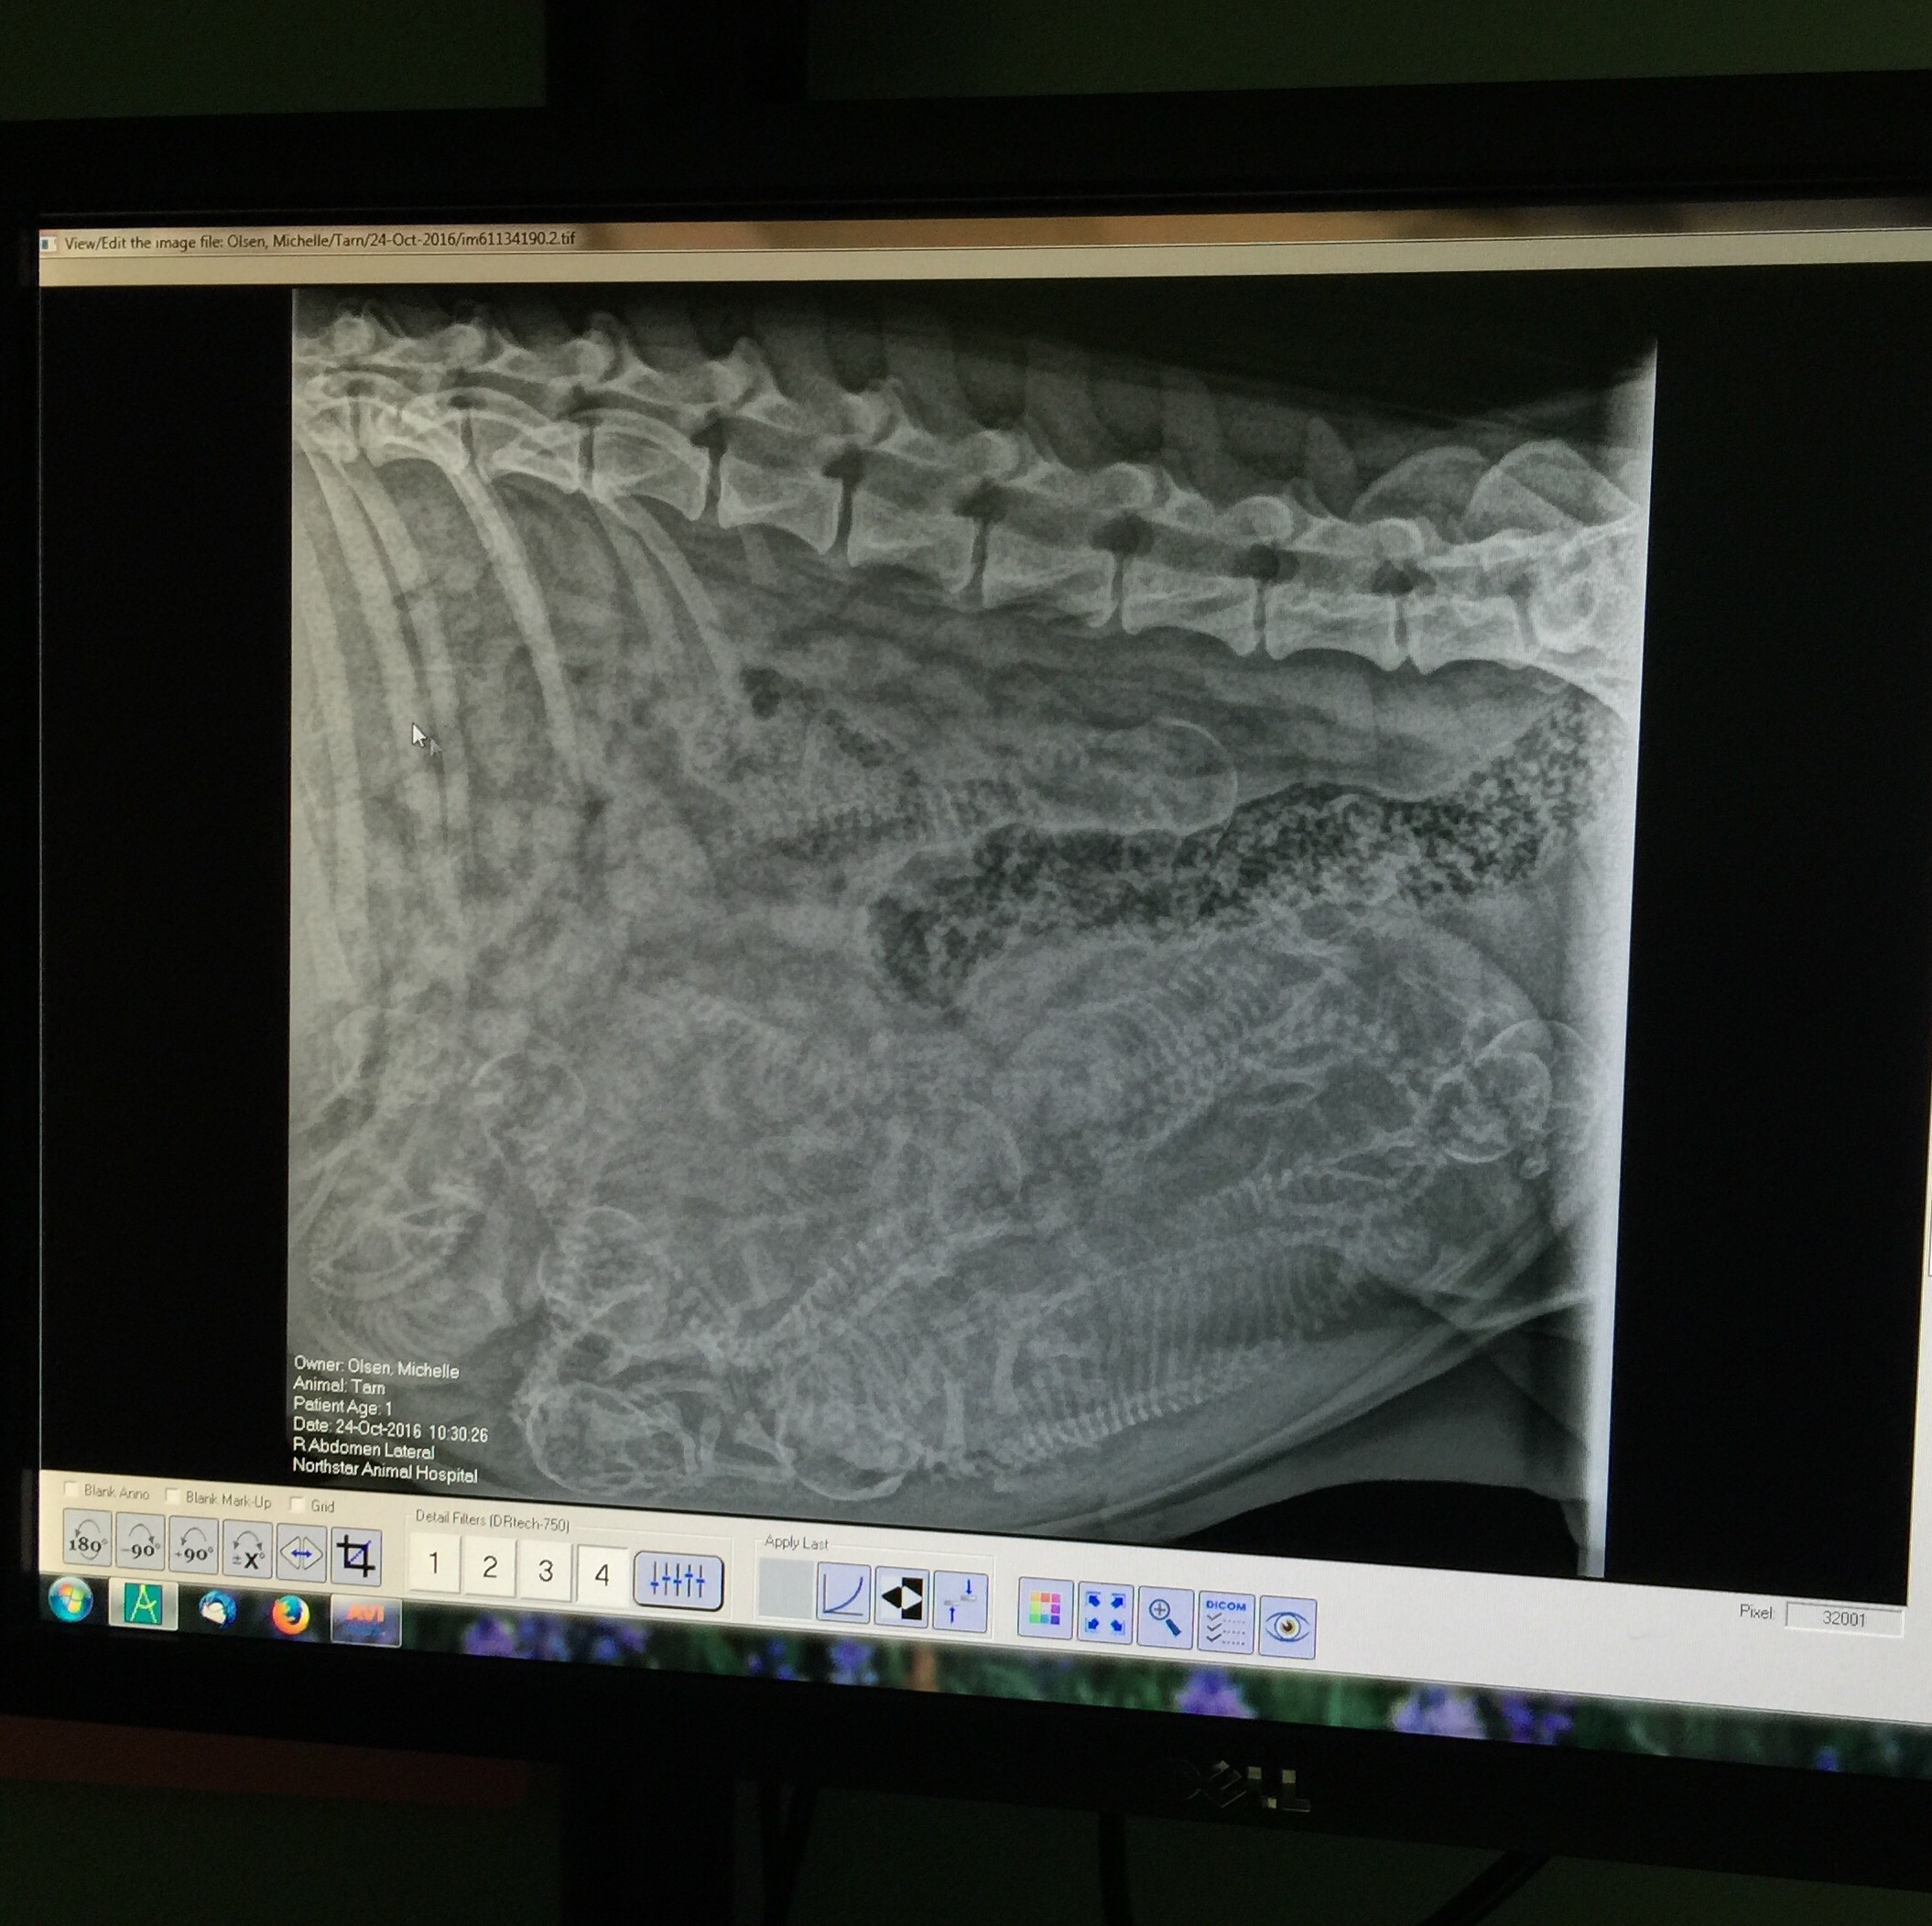

Uncategorized Trick Or Treat Posted by TowerRanchAlaska on October 24, 2016 Tarn is getting close to her due date so we did an x-ray to see how many to expect. We think we see 11 new Maremmas getting ready to make their debut. Happy Halloween! Share this: Share on X (Opens in new window) X Share on Facebook (Opens in new window) Facebook Like Loading... Related